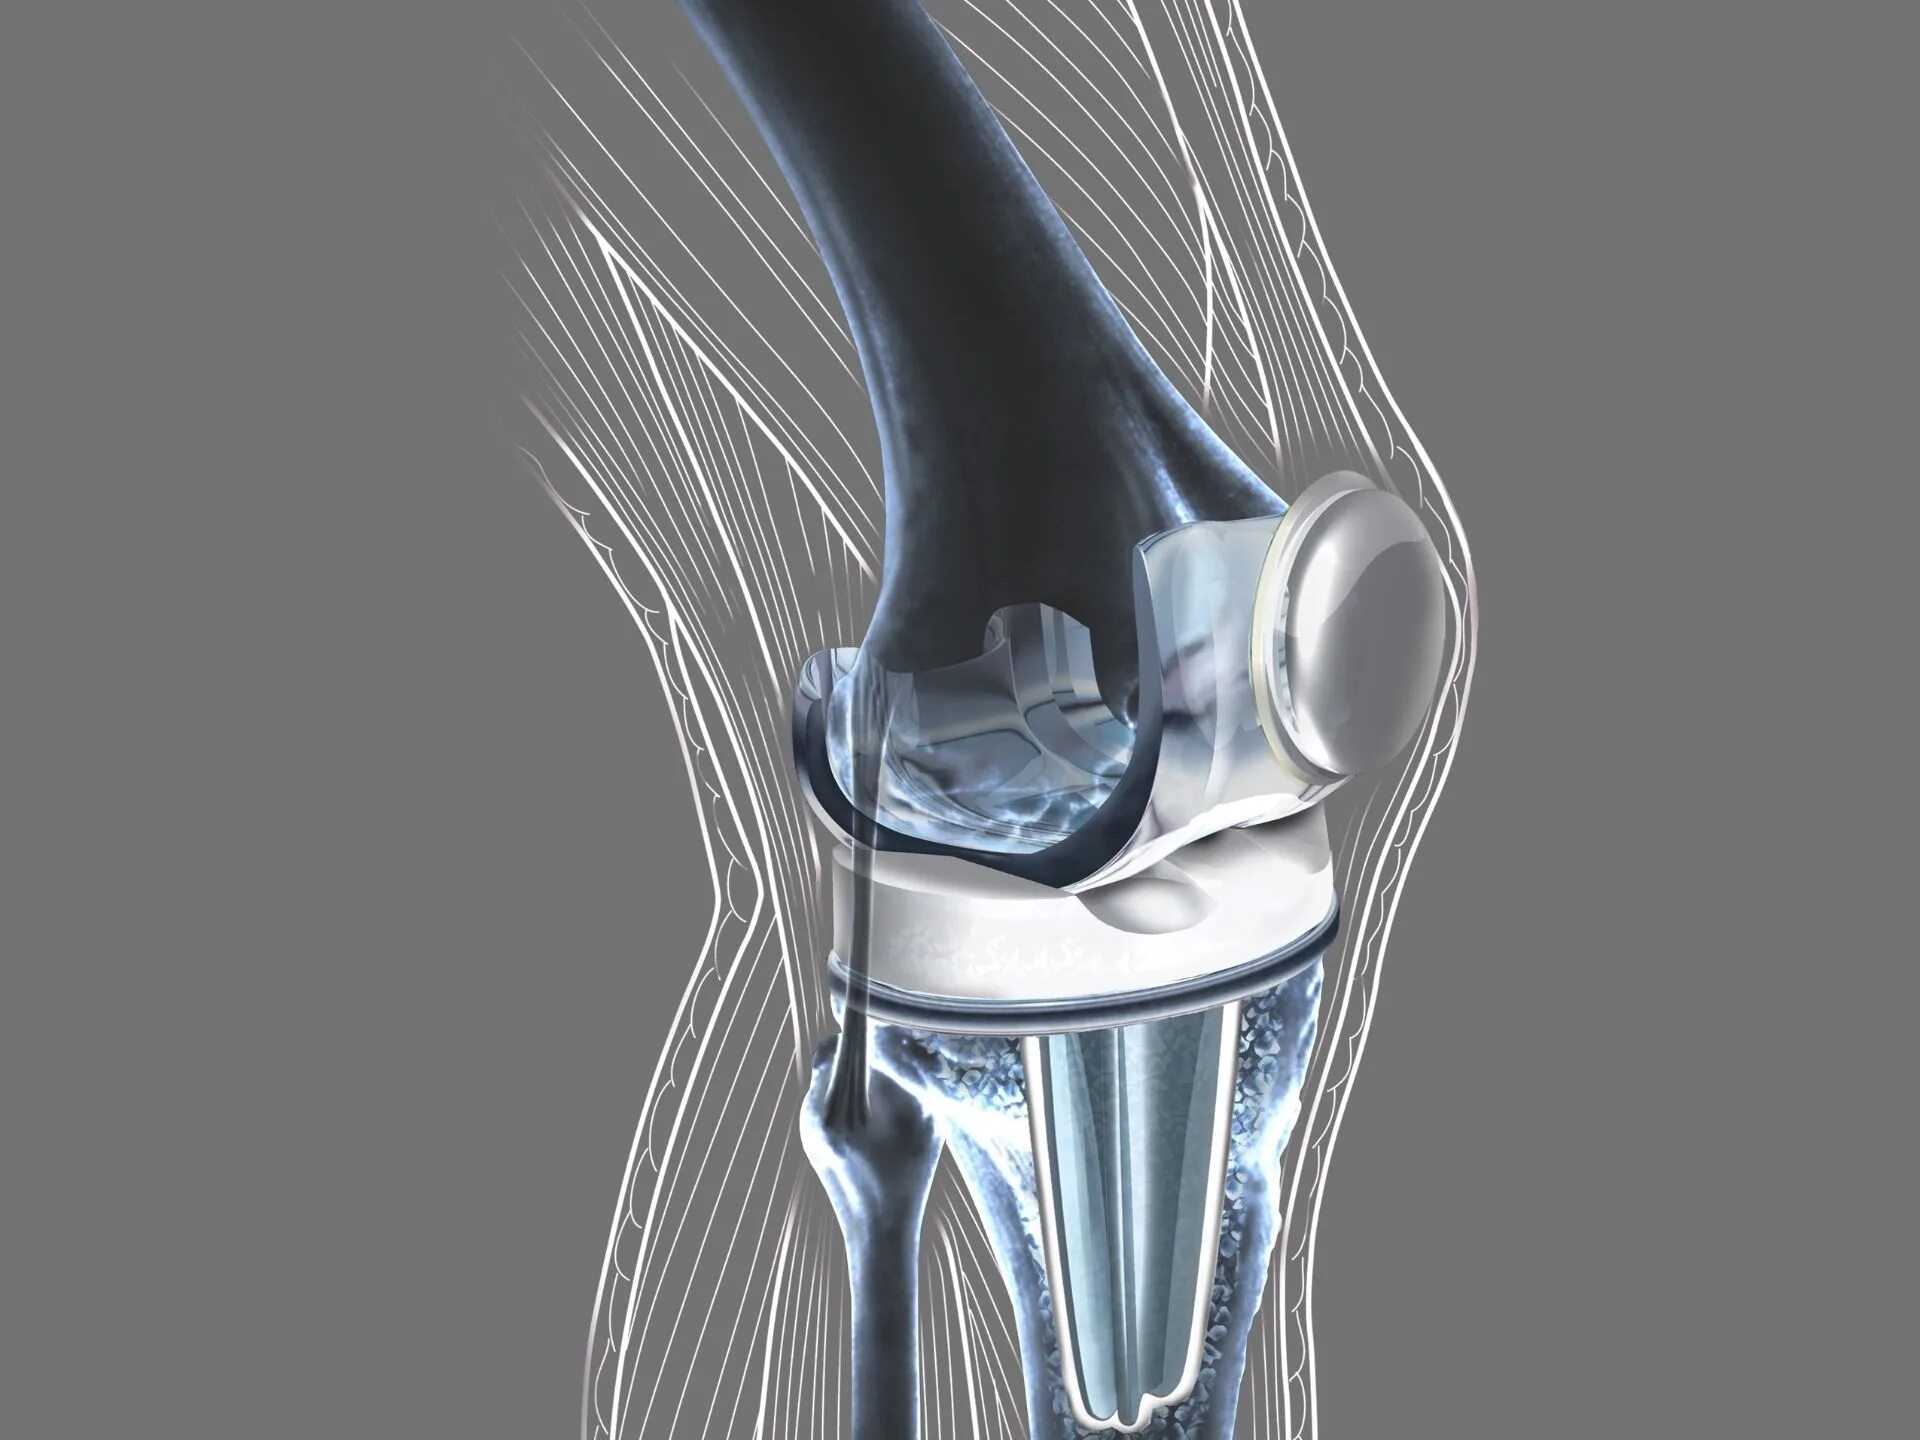

Протезы суставов отзывы